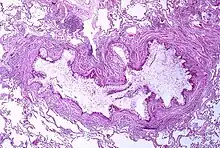

Asthma is the result of chronic inflammation of the conducting zone of the airways (most especially the bronchi and bronchioles), which subsequently results in increased contractability of the surrounding smooth muscles. This among other factors leads to bouts of narrowing of the airway and the classic symptoms of wheezing. The narrowing is typically reversible with or without treatment. Occasionally the airways themselves change.[22] Typical changes in the airways include an increase in eosinophils and thickening of the lamina reticularis. Chronically the airways' smooth muscle may increase in size along with an increase in the numbers of mucous glands. Other cell types involved include T lymphocytes, macrophages, and neutrophils. There may also be involvement of other components of the immune system, including cytokines, chemokines, histamine, and leukotrienes among others.[21]

Although asthma is a chronic obstructive condition, it is not considered as a part of chronic obstructive pulmonary disease, as this term refers specifically to combinations of disease that are irreversible such as bronchiectasis and emphysema.[105] Unlike these diseases, the airway obstruction in asthma is usually reversible; however, if left untreated, the chronic inflammation from asthma can lead the lungs to become irreversibly obstructed due to airway remodeling.[106] In contrast to emphysema, asthma affects the bronchi, not the alveoli.[107] The combination of asthma with a component of irreversible airway obstruction has been termed the asthma-chronic obstructive disease (COPD) overlap syndrome (ACOS). Compared to other people with "pure" asthma or COPD, people with ACOS exhibit increased morbidity, mortality and possibly more comorbidities.[108]